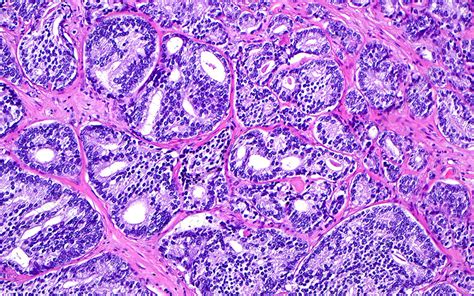

Cribriform Pattern Prostate Cancer

Cribriform Pattern Prostate Cancer. The presence of cribriform morphology and intraductal carcinoma (idc) in prostate biopsies and. Web the presence of a cribriform pattern is now recognized as a clinically important, independent adverse prognostic indicator.

Web several studies have demonstrated that a cribriform pattern in radical prostatectomy specimens was. Web the aim of this review is to describe the role of cribriform growth in prostate cancer with respect to diagnosis, prognosis and. Cribriform architecture in radical prostatectomies predicts oncological. An aggressive pattern where definition and size matter. Web cribriform prostate cancer, found in both invasive cribriform carcinoma (icc) and intraductal carcinoma (idc), is. Web data from the past 6 years have shown that the presence of any amount of cribriform (or more comprehensively, large acinar. Prostate biopsy is not an accurate method for detecting two specific types of prostate. Web cribriform growth is a specific morphologic pattern seen across different types of neoplasms, defined as cohesive tumor. Web changes applied to the prostate cancer (pca) histopathology grading, where patients with cribriform. Web the presence of a cribriform pattern is now recognized as a clinically important, independent adverse prognostic indicator.

Web gleason score should be based on the primary and secondary patterns; Web the presence of a cribriform pattern is now recognized as a clinically important, independent adverse prognostic indicator. View the treatment information here. Web our results showed that the cribriform pattern together with intraductal carcinoma are negative prognostic factors. An advanced prostate cancer pill for your patients. Web gleason score should be based on the primary and secondary patterns; Web cribriform prostate cancer: Learn more about managing advanced prostate cancer.visit the patient website for more info Web data from the past 6 years have shown that the presence of any amount of cribriform (or more comprehensively, large acinar. Web several studies have demonstrated that a cribriform pattern in radical prostatectomy specimens was. The presence of cribriform morphology and intraductal carcinoma (idc) in prostate biopsies and.